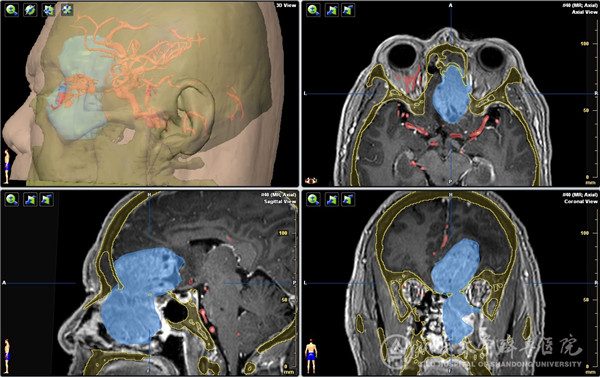

患者48岁,因持续性鼻塞1个半月入院,MR显示右侧鼻颅贯通性肿物,大小约10cmx5cmx4cm,占据右侧额叶、筛窦及整个右侧鼻腔,右侧额窦、蝶窦及上颌窦口受累并堵塞;病变侵犯并突破硬脑膜,周围脑组织及侧脑室受压明显,脑水肿范围大、脑中线结构左移,肿瘤包绕双侧额眶动脉,与大脑前动脉及视神经关系密切。术前活检病理提示嗅神经母细胞瘤。患者入院前已辗转省内及北京多家绿帽社,但因手术难度大、风险高,均未能得到治疗。

入院后李学忠教授组织耳鼻喉科、神经外科、神外重症监护及麻醉科进行了充分讨论,手术由冯昕及倪石磊共同主刀完成,戚其超医师和徐佳宁医师担任助手。术中开放双侧全组鼻窦并彻底切除鼻腔鼻窦的肿瘤,显露并保护双侧眶尖、前颅底、视神经及颈内动脉管,后采用美国匹兹堡大学内镜颅底中心“双人四手”技术操作,电凝双侧筛前、筛后动脉阻断肿瘤供血,仔细分离并完整切除颅内肿瘤及肿瘤起源的嗅球、嗅束,完好地解剖并保护被肿瘤包绕的大脑前动脉重要分支。肿瘤切除后前颅底缺损5cmx5cm,同期取右股外侧阔筋膜及鼻腔带蒂粘膜瓣重建颅底缺损。该肿瘤血运极为丰富,但由于手术策略成功,术中仅出血约500ml;同时手术全程经鼻腔完成,没有颌面部刀口;术中确切的颅底重建阻隔了有菌的鼻腔环境,为患者的快速康复扫清了最后障碍。术后患者转入神外重症监护病房,由黄齐兵主任医师、张源医师、晏骖主治医师共同监护度过了术后恢复期,后转回耳鼻喉科病房,患者各项神经功能保护良好,恢复到正常生活状态,于近日康复出院,患者及家属非常满意手术效果。术后病理为高级别嗅神经母细胞瘤。